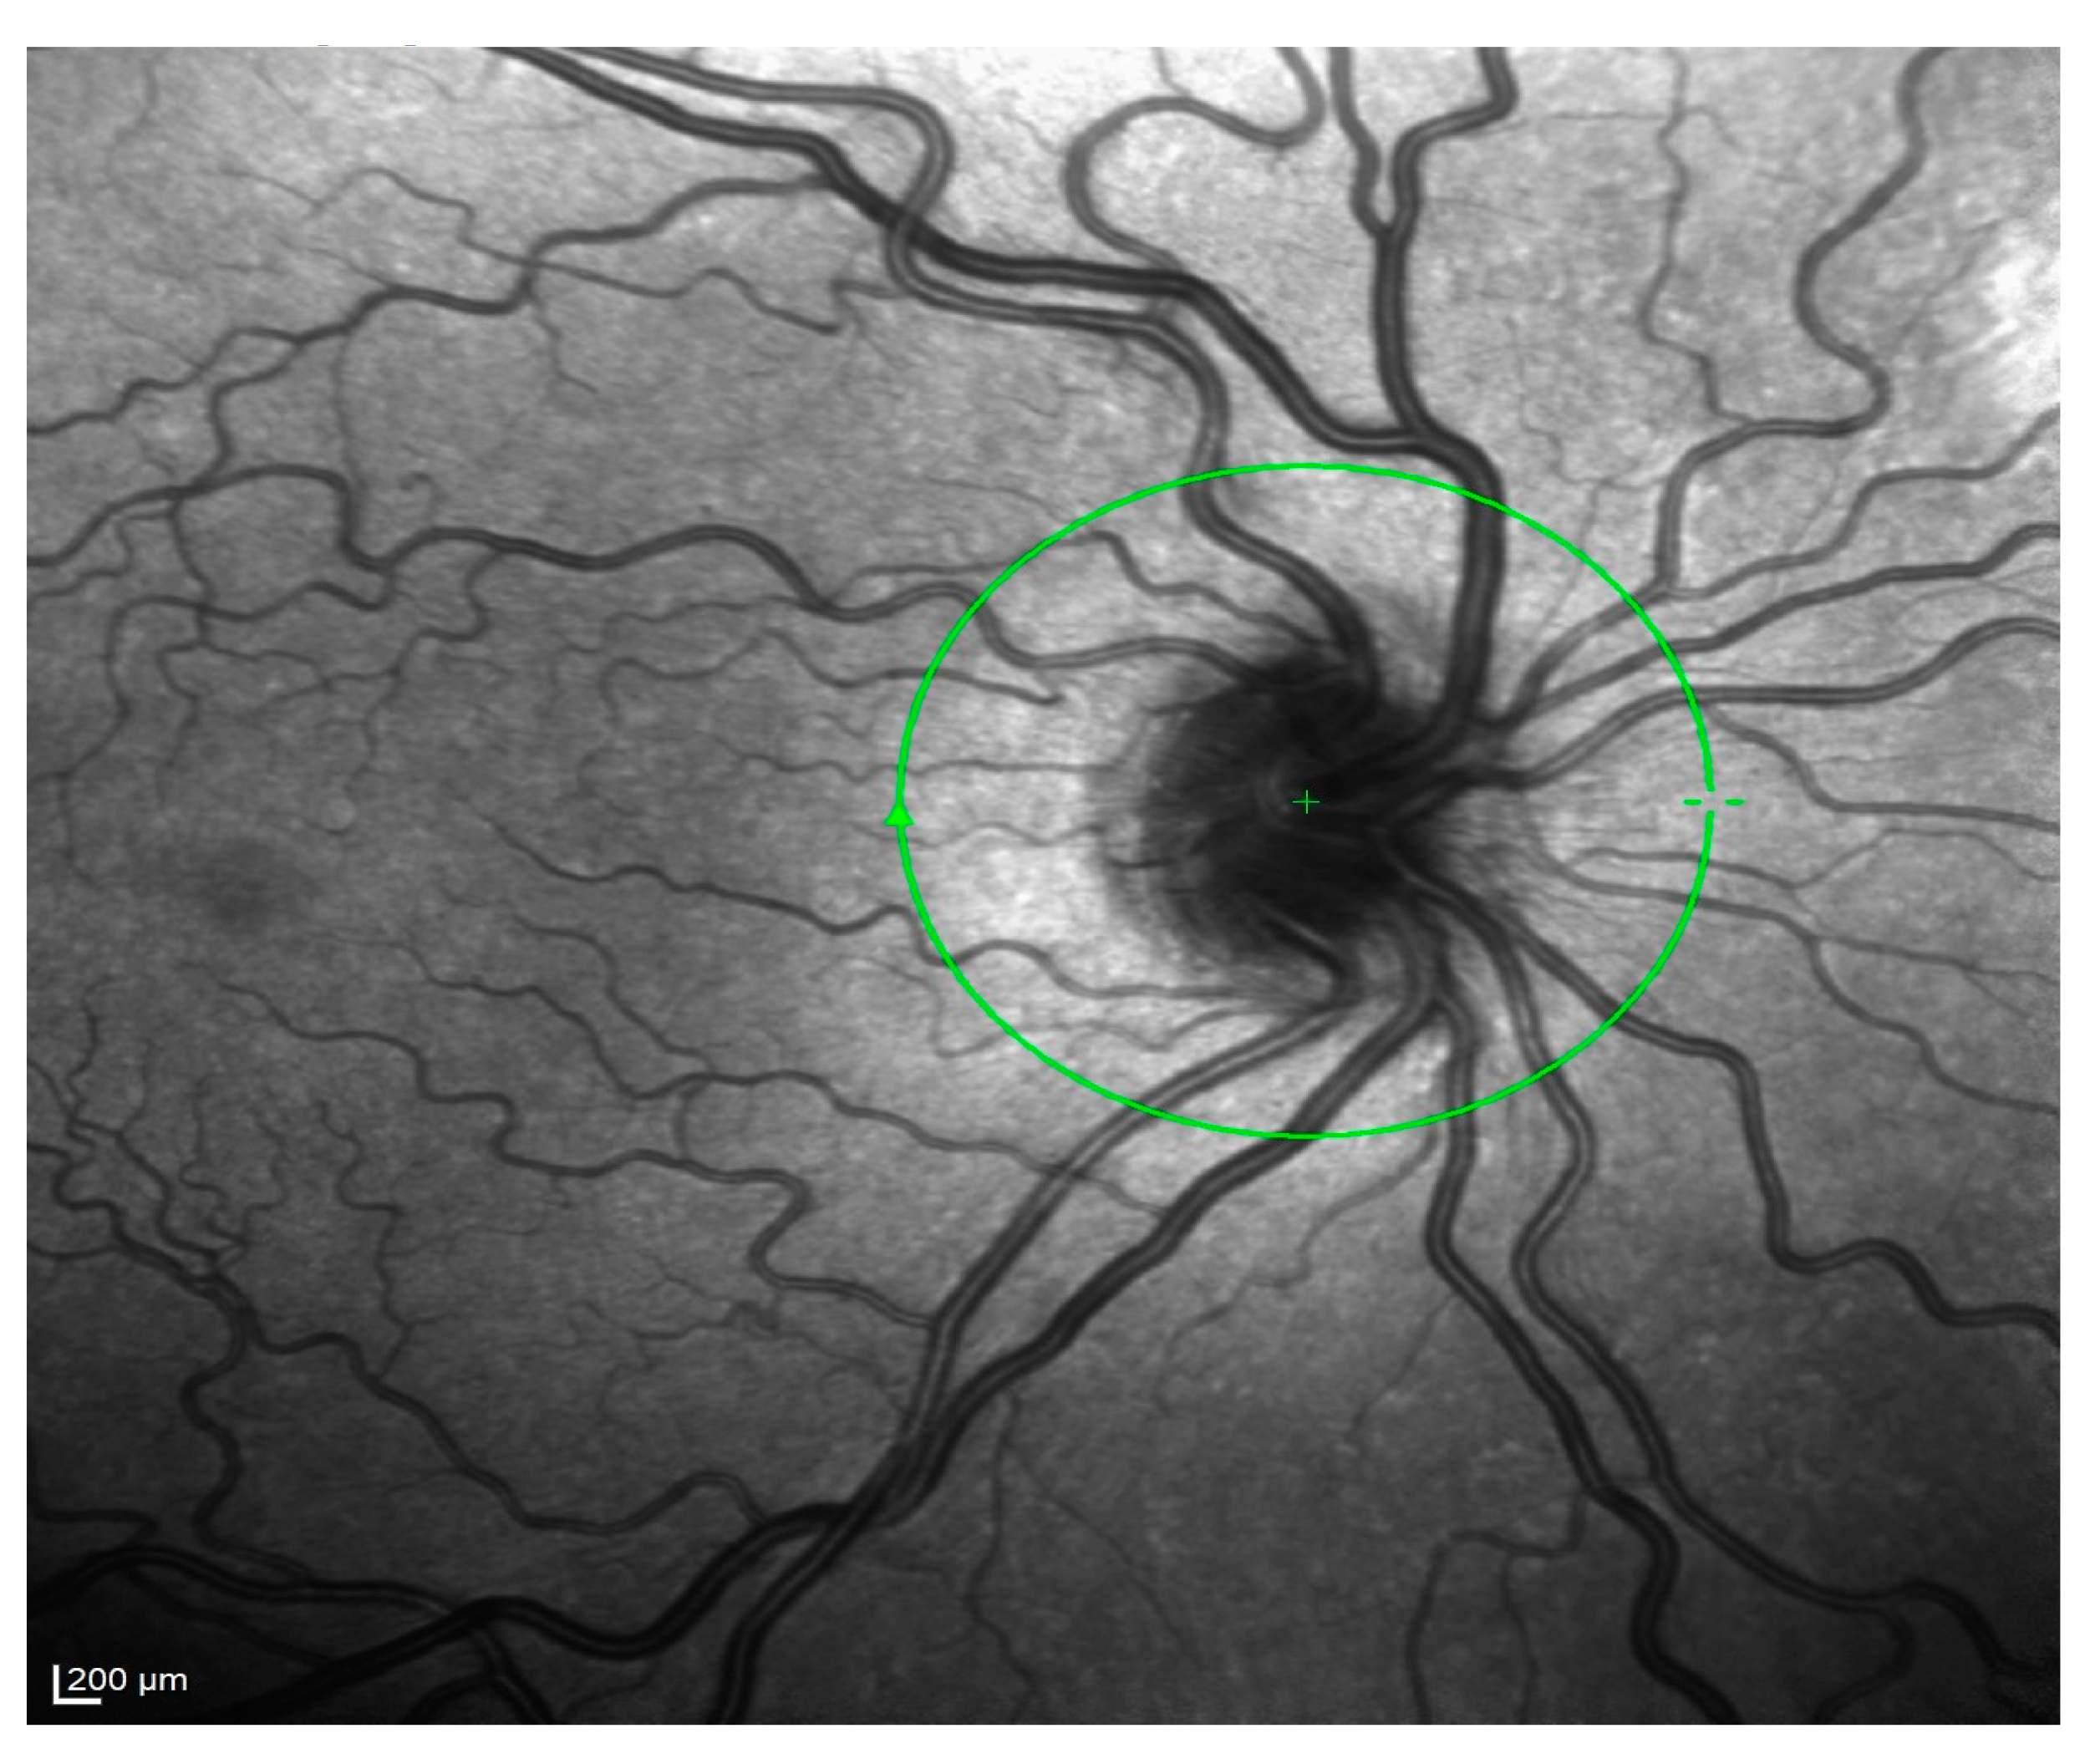

- Hernández-Quintela, E.; Mayer, F.; Dighiero, P.; Briat, B.; Savoldelli, M.; Legeais, J.-M.; Renard, G. Confocal microscopy of cystic disorders of the corneal epithelium. Ophthalmology 1998, 105, 631–636. [Google Scholar] [CrossRef]

- El Sanharawi, M.; Sandali, O.; Basli, E.; Bouheraoua, N.; Ameline, B.; Goemaere, I.; Georgeon, C.; Hamiche, T.; Borderie, V.; Laroche, L. Fourier-domain optical coherence tomography imaging in corneal epithelial basement membrane dystrophy: A structural analysis. Am. J. Ophthalmol. 2015, 159, 755–763. [Google Scholar] [CrossRef]

- Rosenberg, M.E.; Tervo, T.M.; Petroll, W.M.; Vesaluoma, M.H. In vivo confocal microscopy of patients with corneal recurrent erosion syndrome or epithelial basement membrane dystrophy. Ophthalmology 2000, 107, 565–573. [Google Scholar] [CrossRef] [PubMed]

- Kobayashi, A.; Yokogawa, H.; Sugiyama, K. In vivo laser confocal microscopy findings in patients with map-dot-fingerprint (epithelial basement membrane) dystrophy. Clin. Ophthalmol. 2012, 6, 1187–1190. [Google Scholar] [CrossRef] [PubMed][Green Version]